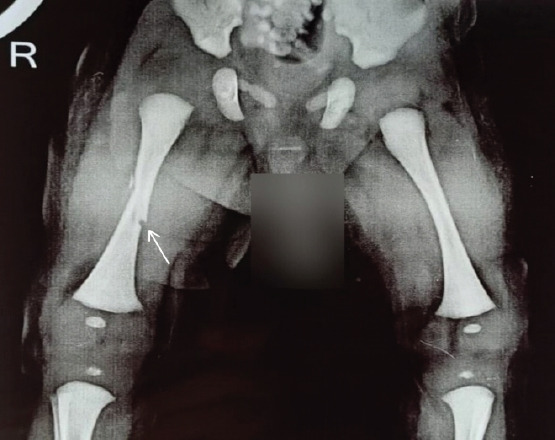

Case report: A 3915 g male child born at 38 weeks and 4 days of gestation to a primigravida aged 31 years by emergency Lower Segment Cesarean Section for Premature Rupture of Membrane with breech presentation. During extraction, the newborn sustained a fracture to his right femur shaft. X-rays confirmed the diagnosis. The fracture was treated successfully with a toe-groin cast for 25 days with complete healing.

Conclusion: As compared to vaginal breech delivery, cesarean section reduces the risk of traumatic birth injuries; however, it does not completely eliminate the possibility of birth injuries and long bone fractures in newborns. Orthopedic opinion must be sought, if the obstetrician and neonatologist suspect any birth trauma in difficult deliveries. Immobilization of the limb leads to complete healing of the fracture without any sequel.